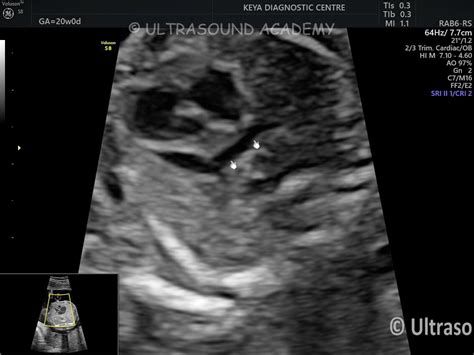

TAPVC SUPRACARDIAC TYPE – Case By Dr. Nitin Jadhav

ultrasoundacademy.in